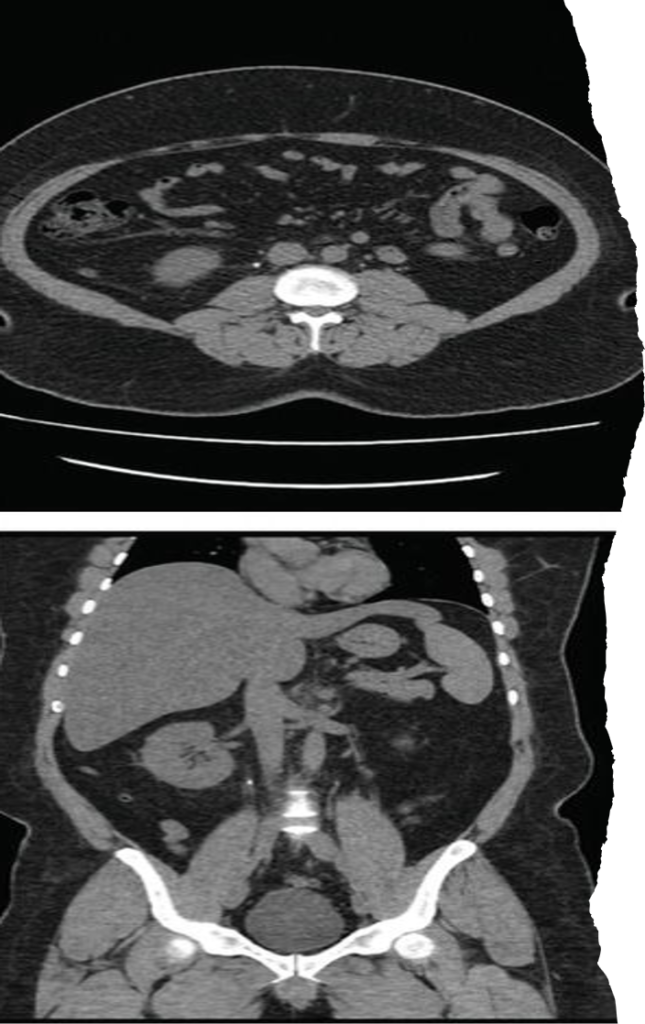

CT KUB axial and coronal sections demonstrating a left renal pelvis calculus (a and b) and left distal ureteric calculus (c).

Plain CT KUB showing right staghorn and giant bladder calculus measuring 9.5 × 9.4 × 11.1 cm³.

- Large branching calculus occupying renal pelvis and calyces.

- Usually composed of struvite.

- Associated with recurrent UTI.

- Suggests long-standing disease.